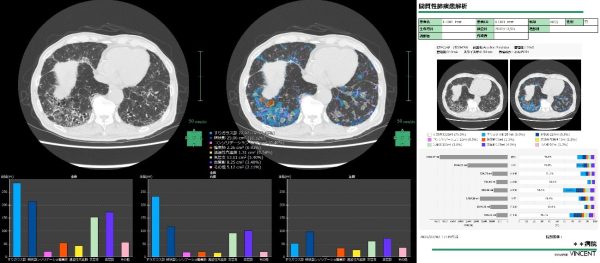

脳区域解析や間質性肺疾患解析においても医療現場のニーズに対応し、セグメンテーションした領域の定量化とレポート作成機能を新たに搭載した。幅広いシーンで活用できる3Dワークステーションとして、アップデートしている。

2025年にリリースした間質性肺疾患解析にも新たにレポート機能を搭載し、CT画像から定量評価した結果をレポートとしてアウトプットする一連のフローを「SYNAPSE VINCENT」で行うことができるようになる。